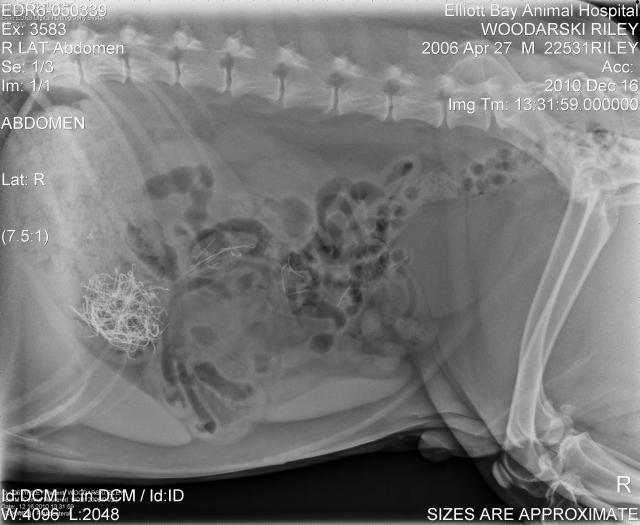

Apparently, the painted styrofoam berries on a mini wreath meant to adourn a present was too intoxicating for the little guy to resist.  But Riley didn’t stop there. He had also eaten the ribbon, paper, silk leaves and WIRE!  The red dye evidence was all over his face, paws and tongue.  In four years this dog has NEVER – I repeat – NEVER eaten anything in the house.  Shoes, handbags, boxes, recycling, books all rest safely on the floor, never to be bothered.  Who knew a 2″ wreath would prove so enticing?

After a visit to his home-away-from-home, Elliot Bay Animal Hospital, we decided to take a easy approach hoping the situation would resolve itself with the help of a high fiber diet for 36 hours.  Worked like a charm on the styrofoam balls; not so much with the wire. Worried about possible puncture wounds, Riley checked into the VCA Veterinary Specialty Center  in Lynnwood Friday night for an endoscopy.  Waiting to be seen in the ER was difficult because there were quite a few dogs coming in with more critical issues than ours.  The visible concern, worry and unease on the owners’ faces made me so sad.  I want to believe all of them were as lucky as us and are doing much better today. Four hours, four calls from the vet and three x-rays later, Riley was wire free!  I won’t begin to tell you what Thursday thru Monday cost, but I will say I could have probably got three or four pairs of Pradas.  Thank goodness for pet insurance.  If you have a cat or dog and don’t have it…get it!  It is more affordable than you would think.  And it has been a Godsend for us in the last year.

pre-endoscopy…wire + balls oh my!